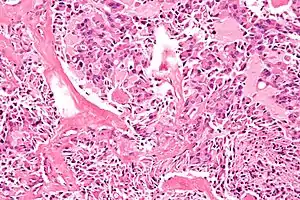

![]() Мікрофотознімок медулярного раку щитоподібної залози, однієї з найчастіших складових МЕН-2А та МЕН-2Б (фарбування г-е). Мікрофотознімок медулярного раку щитоподібної залози, однієї з найчастіших складових МЕН-2А та МЕН-2Б (фарбування г-е). | |